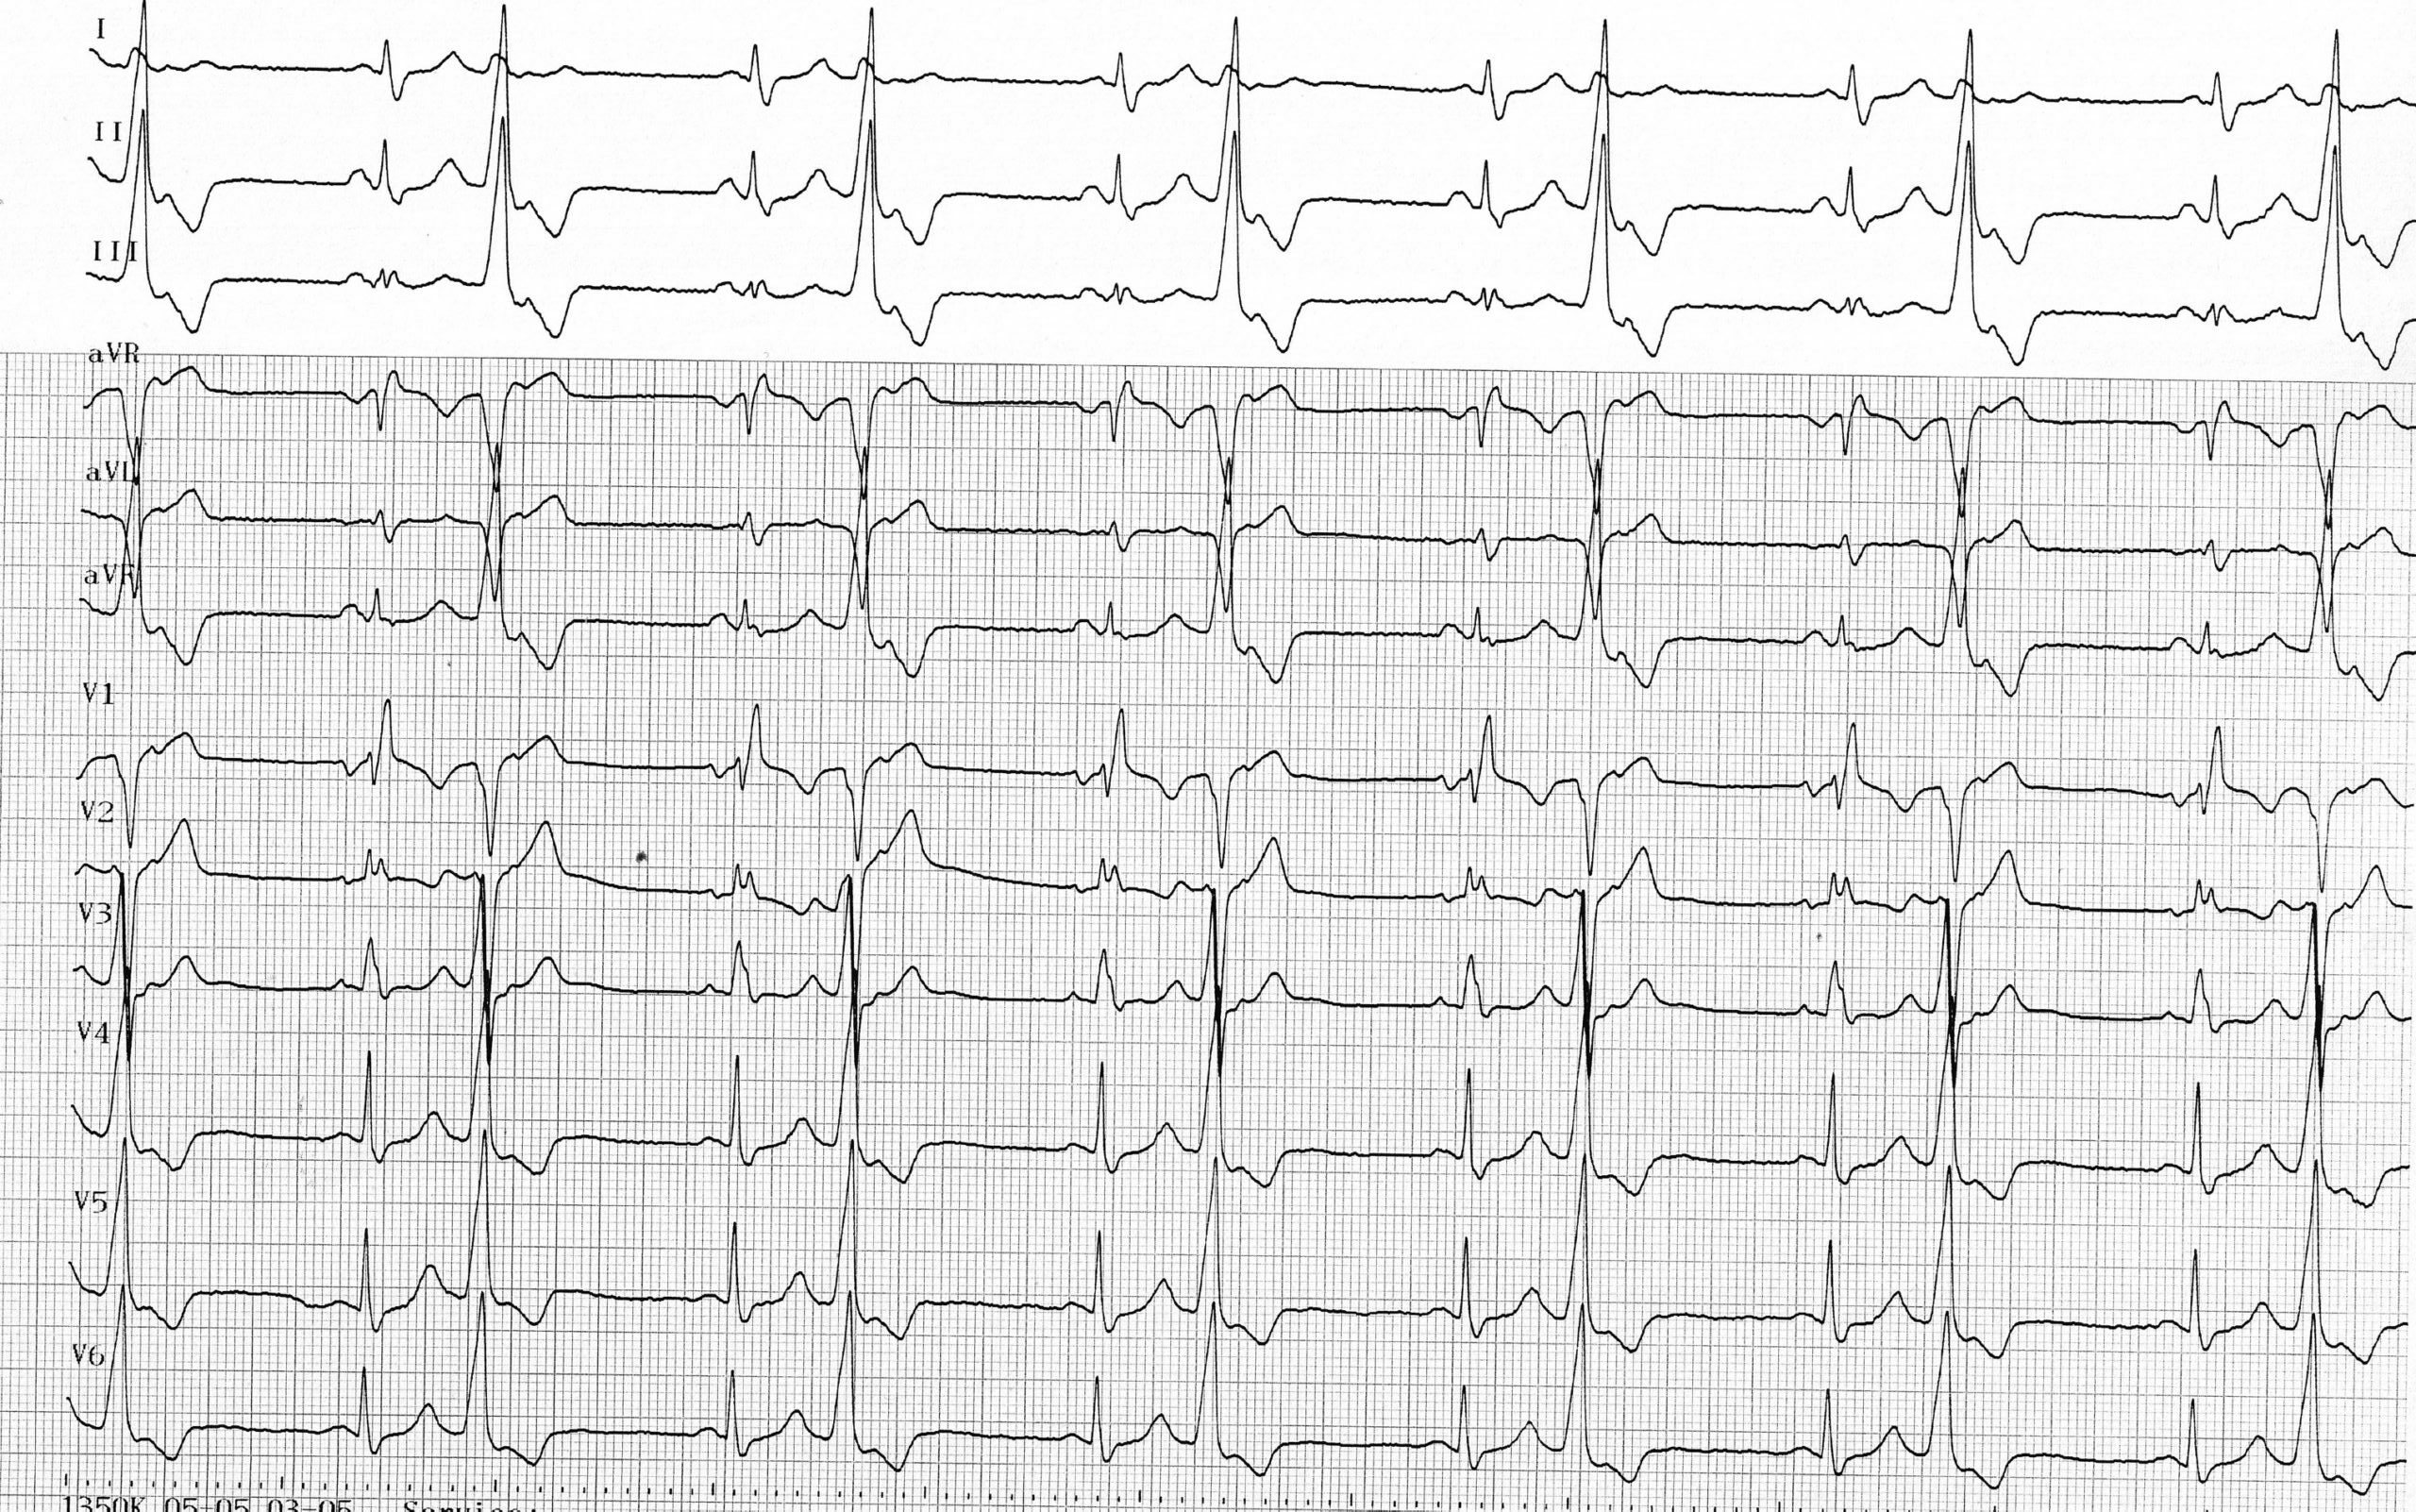

Les patients présentant des extrasystoles ventriculaires peuvent être parfaitement asymptomatiques, le diagnostic se faisant à la prise de pouls avec mise en évidence d’une irrégularité et de battements prématurés. Comme chez ce patient, la prise de pouls peut conduire au diagnostic de bradysphygmie qui correspond à un ralentissement du pouls en raison de l’inefficacité hémodynamique des extrasystoles, le pouls restant régulier si l’extrasystolie est bigéminée. Cette bradycardie effective peut entrainer une symptomatologie type asthénie ou dyspnée d’effort.

Le nombre d’extrasystoles sur une journée ne constitue pas un facteur pronostic majeur. La charge en extrasystoles est en revanche déterminante concernant l’éventuel retentissement sur la fonction cardiaque. Le bigéminisme observé chez ce patient peut, si il se maintient, être responsable du développement d’une véritable cardiopathie rythmique. La caractérisation de l’extrasystolie peut donc être complétée par la réalisation d’un Holter-ECG des 24 heures qui permet une évaluation quantitative avec mesure de la charge en extrasystoles sur 24 heures, mais également qualitative avec le nombre de morphologies différentes (extrasystoles monomorphes ou polymorphes), le couplage, l’existence de formes répétitives (présence de doublets, triplets, et/ou de salves), le lien avec la fréquence cardiaque (mécanisme catécholergique, vagal ou indéterminé), l’alternance jour-nuit (distribution nocturne et diurne). Plus que le nombre absolu d’extrasystoles, il semble que la présence d’activités répétitives à couplage très courts, permettent d’identifier les patients les plus à risque.